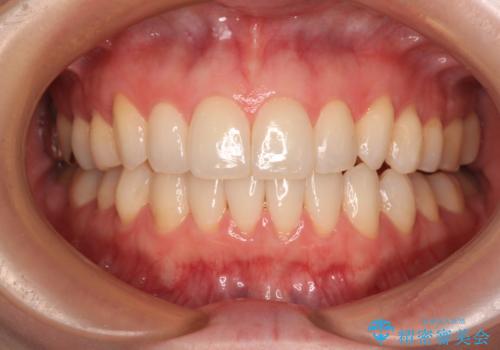

前歯のデコボコをインビザラインで改善

- 前歯のデコボコや八重歯の様になっていることを気にして来院された患者様です。

犬歯捻れて前方に飛び出しており、下顎前歯もそれに沿うようにデコボコとなっていました。

IPR(歯と歯の間を削る処置)によりスペースを獲得して上下顎前歯のデコボコを改善し、前歯が前方に突出しないように設定した上で、インビザラインにて矯正治療を行うこととしました。

途中体調を崩され、長い期間矯正治療を休むことになったため4年半ほどの治療期間がかかりました。